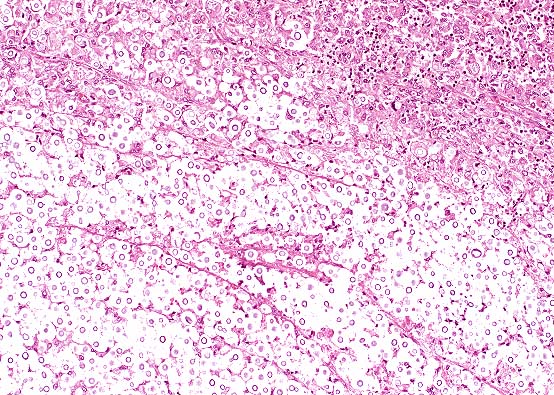

Expansion of the nasal submucosa by an infiltrate of macrophages, and lesser lymphocytes and plasma cells in a 1-year-old dog with cryptococcosis. (HE, 100X, 98K)

Characteristic "soap-bubble" appearance of Cryptococcus neoformans infection. This appearance is the result of production of a thick capsule by the yeast. Varying degrees of inflammation may be seen in animal tissue. (HE, 200X, 124K)

Conference Note: Participants agreed that the morphology of the budding yeast is consistent with Cryptococcus neoformans. In H&E stained sections, C. neoformans appears thin-walled, slightly basophilic and spherical, with single narrow-based buds. The fungus is surrounded by a wide clear zone; the shrunken capsular material stains positively with mucicarmine and the fungal wall stains with PAS. In some sections, scattered foci of osteonecrosis of the turbinates were noted.

Cryptococcosis occurs worldwide in many species, but cats are affected most frequently. Cats that are immunologically compromised, such as those infected by feline immunodeficiency virus or feline leukemia virus, those treated with corticosteroids or those that are malnourished, are most susceptible. Infection is acquired in most instances through inhalation of contaminated dust, with localization in the nasal turbinates or lungs sometimes followed by systemic dissemination. Cryptococcal mastitis in cows is believed to be initiated by local inoculation. In cases of systemic infection, a broad spectrum of lesions and clinical signs have been reported; however, rhinitis, pneumonia, ulcerative skin lesions, encephalitis and ocular infections are the most prevalent. The pulmonary lesion is a multifocal granulomatous pneumonia. CNS infection may involve the meninges and neuropil. The characteristic gross appearance of cryptococcal lesions is that of small, gelatinous, white foci. The microscopic features of the infection vary from little cellular reaction and many organisms (gelatinous form) to a more granulomatous reaction characterized by macrophages, giant cells, lymphocytes and a fibrous stroma.